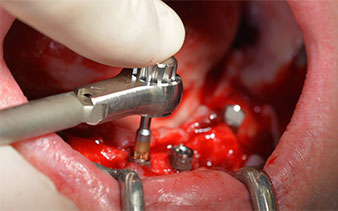

El protocolo quirúrgico de los implantes utilizados (SKY, bredent medical) prescribe una velocidad de 1 200/rpm para las perforaciones piloto (figs. 7-9).

Este valor se corresponde con la posición siguiente del ajuste predefinido en Implantmed. Aquí se aprecia la inclinación de aproximadamente 45 grados del contra-ángulo de W&H hacia medio caudal en la región de la pieza 45 para preservar el nervus mentalis. El foramen mentale sirve como orientación anatómica para todas las perforaciones en esta zona. Las perforaciones siguientes se realizaron con una velocidad reducida de 300/rpm (figs. 10 y 11).